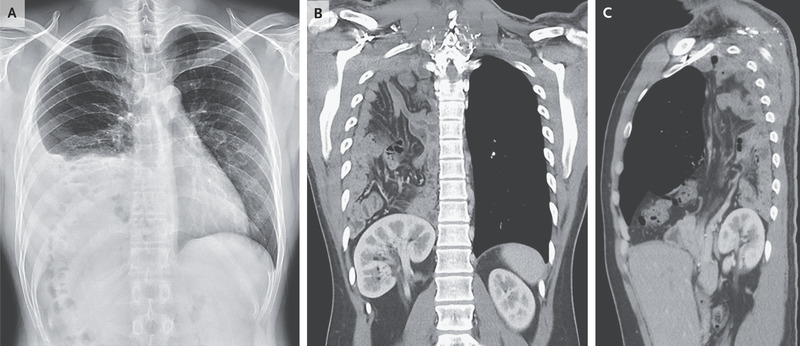

This article describes the case of a 25-year-old man who was referred to the emergency department because of abnormal results on the chest radiograph. Based on the investigation findings, the doctors diagnosed the patient with a congenital diaphragmatic hernia. Read more about it here: https://bit.ly/3TClbaB